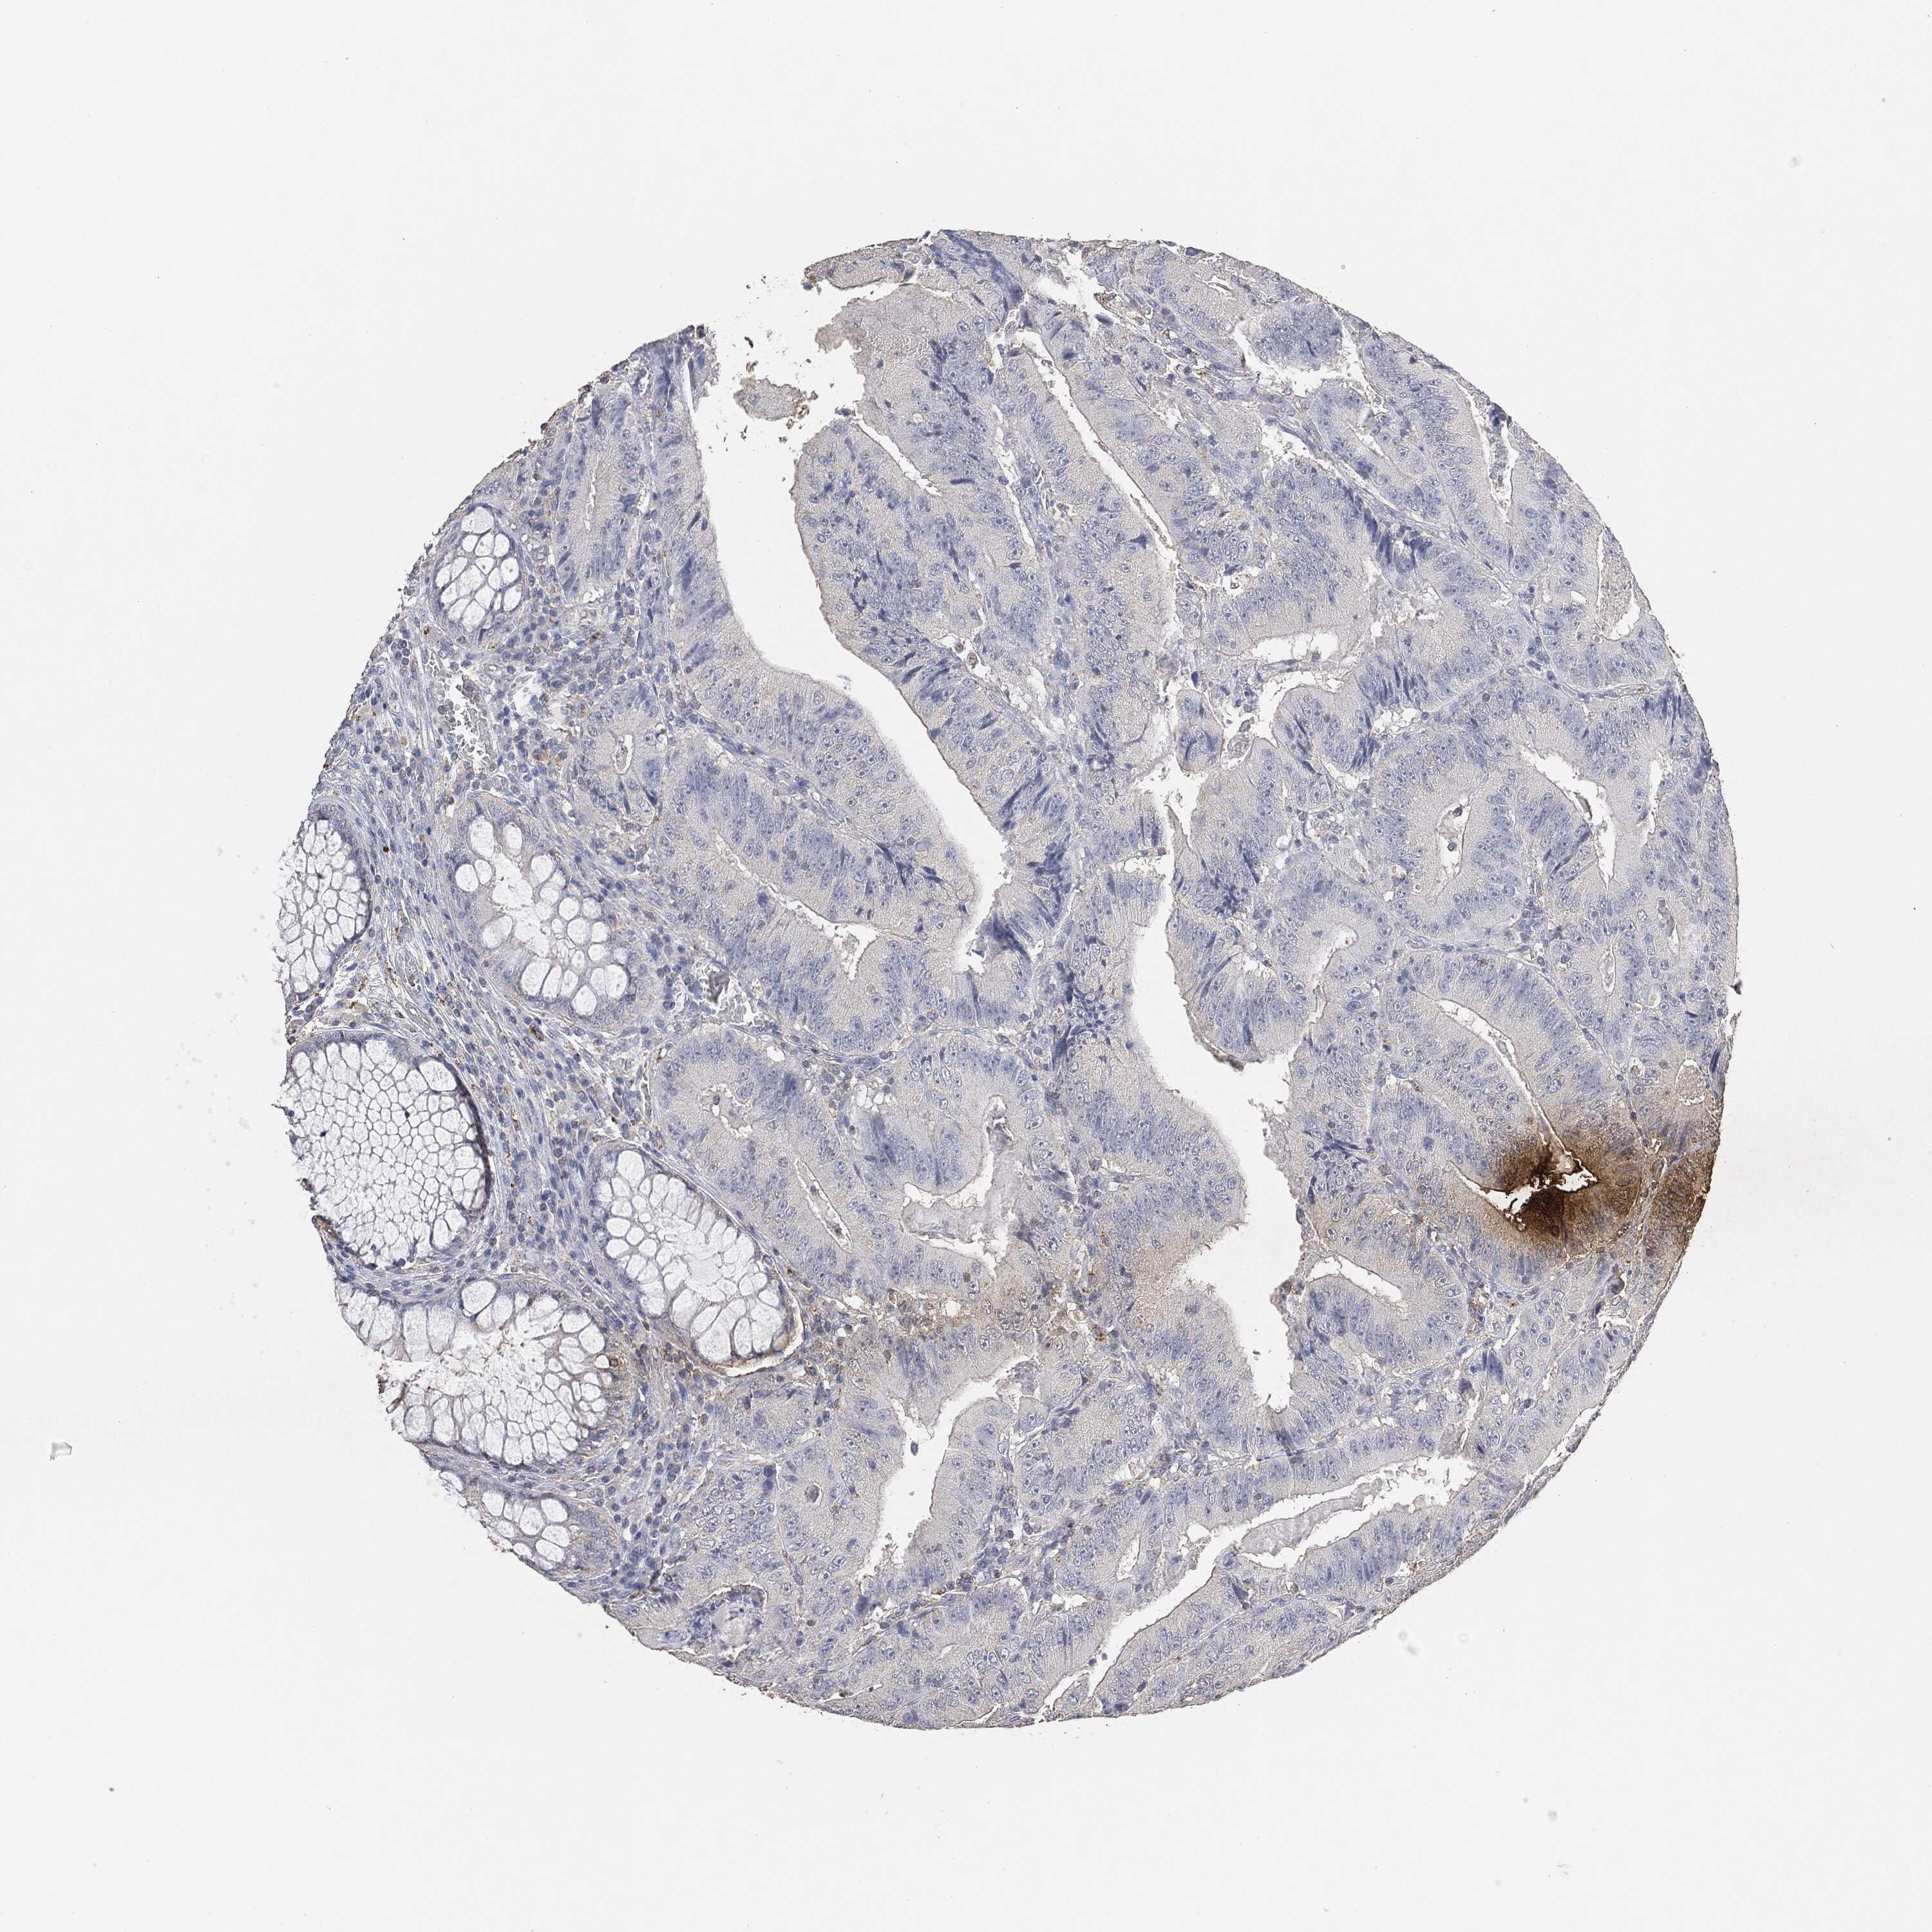

CANCER COLORECTAL CANCER Show tissue menu

Colorectal cancer

Human cancer

Colon adenocarcinoma